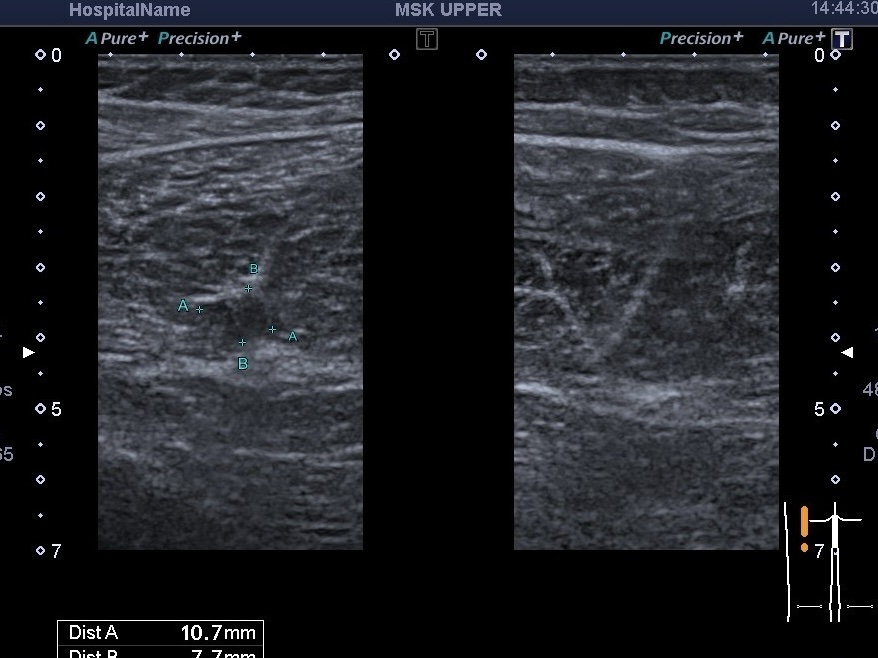

На скане как раз мы видим повреждения длинной головки бедра(сухожильно-мышечный переход) и сухожилия полусухожильной мышцы. Ісуществуют разные классифиации степеней повреждений мышц. Все они ориентируются на процент повреждения относительно площади поперечного сечения (1,2,3 степень и 4ст.- разрыв). Кроме степени повреждения, УЗИ оценивает наличие гематомы, а также наличие тромбоза близлежащих сосудов.